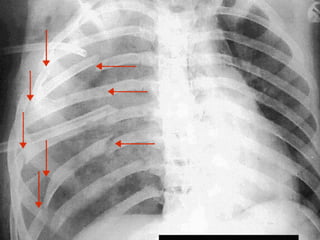

F I N D T H E F L A I L

S E G M E N T

L E T S T R Y A N X R A Y

L O O K C A R E F U L L Y

F L AI L C H E S T • OCCURS WHEN SEGMENT OF FRACTURED RIBS ARE SEPARATED FROM THE CHEST WALL • NOTE THE PARADOXICAL MOVEMENT • MAIN AIM OF TX IN CASUALTY IS PAIN CONTROL AND ICD • PAIN CONTROL VIA INTERCOSTAL NERVE BLOCK • SURGEONS AND ICU MUST BE INVOLVED EARLY, OFTEN PTS REQUIRE VENTILATION • OFTEN THERE ARE ASSOCIATED LUNG CONTUSIONS, HAEMOPNEUMOTHORAX AND CARDIAC CONTUSIONS

F I ND T H E F L A I L S E G M E N T L E T S T R Y A N X R A Y